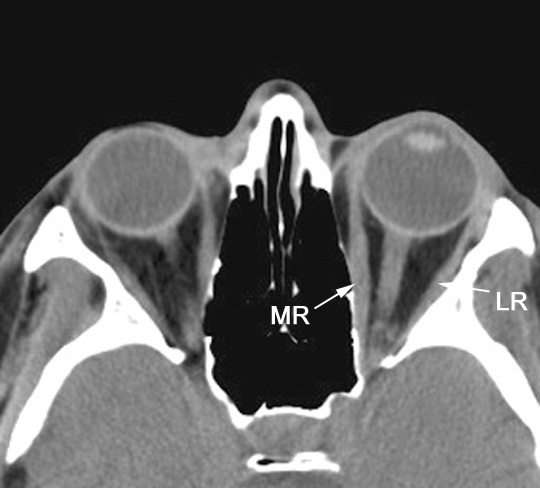

Identify the medial and lateral recti. Click the image for labeling.